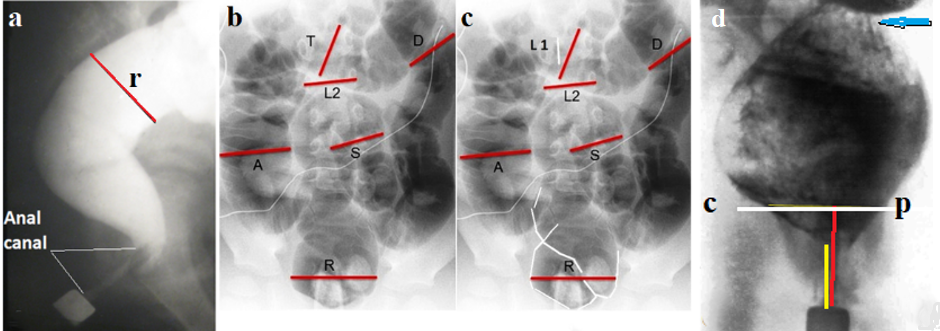

Figure 1 illustrates lateral radiographs of the anorectal region in patients with varying degrees of megacolon.

Figure 1. Lateral radiographs of the anorectal region in patients with varying degrees of megacolon compared with normal.

a) In the normal rectum, forward rotation shifts the axis of the anal canal anteriorly relative to the anterior rectal wall, forming an acute anorectal angle.

b) Grade 1 megacolon. Rectal dilation results in loss of the horizontal branch of the rectum. Edema of the puborectalis muscle (PRM) creates concavity in the posterior rectal wall (arrow) due to compression of the PRM by wide fecal masses that struggle to pass through the anal canal.

c) Grade 2 megacolon. Further rectal stretching нивелирует the horizontal portion of the rectum. Due to PRM weakening, contrast penetrates the anal canal only when rectal pressure increases.

d) Grade 3 megacolon. Severe rectal dilation is accompanied by marked constant shortening of the anal canal, consistent with fixed descending perineum syndrome (DPS).

e) Grade 3 megacolon with DPS. A thin horizontal line indicates the width of the upper anal canal, which does not participate in fecal retention due to the stretching and weakening of the PRM. It is narrower than the rectum since its expansion is limited by pelvic floor musculature.

As can be seen from the comparison of all radiographs, the value of the anorectal angle cannot be used to assess the state of the anorectal function. At the same time, shortening of the anal canal relative to the age norm is convincing evidence of damage to the PRM, which leads to impaired fecal continence. We determined the degree of megacolon using the formula: